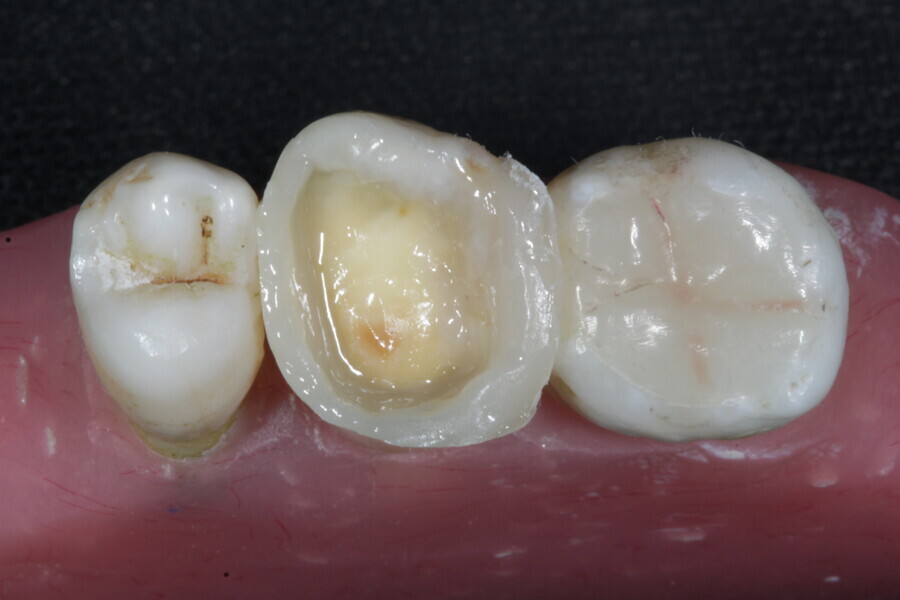

1. direct restoration using a fibre-reinforced flowable composite and membrane cube after endodontic treatment (Figs. 21–35); and

1. restoration reinforcement of a vital tooth with a fibre-reinforced flowable composite and membrane (Figs. 36–45).

Example 3—Restoration reinforcement of a vital tooth with a fibre-reinforced flowable composite and membrane.